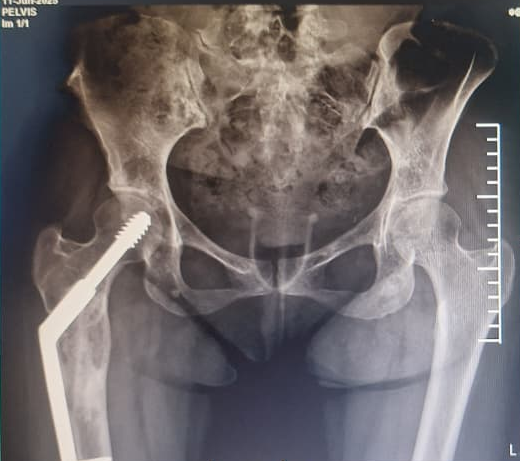

In 2022, the patient presented with progressive pain and restricted range of motion of the right hip following minor trauma. She was re-evaluated clinically and imaging was done. Radiographs (Fig 4 ) and MRI (Fig 5) revealed an expansile lytic lesion of the right proximal femur consistent with intraosseous hemangioma. Due to risk of pathological fracture we planned for fixation of right proximal femur. She underwent right proximal femoral bone excision biopsy and dynamic hip screw fixation with iliac–fibular strut bone grafting (Fig 6). Post-operative period was uneventful. Started partial weight bearing after 45 days followed by full weight bearing by 90 days. Very good radiological incorporation of graft noted and fixation was stable radiologically (Fig 7). Histopathology report suggestive of benign bone hemangiomatous tissue without any features of malignancy (Fig 8).

• 2022: Lytic right proximal femur lesion with risk of pathological fracture (Fig 4).

Intervention

The patient underwent right proximal femur bone excision biopsy, dynamic hip screw fixation, and iliac–fibular strut bone grafting to prevent structural collapse and improve mechanical stability (Fig 6). Post-operative imaging confirmed adequate consolidation over 3 year follow-up period (Fig 10).